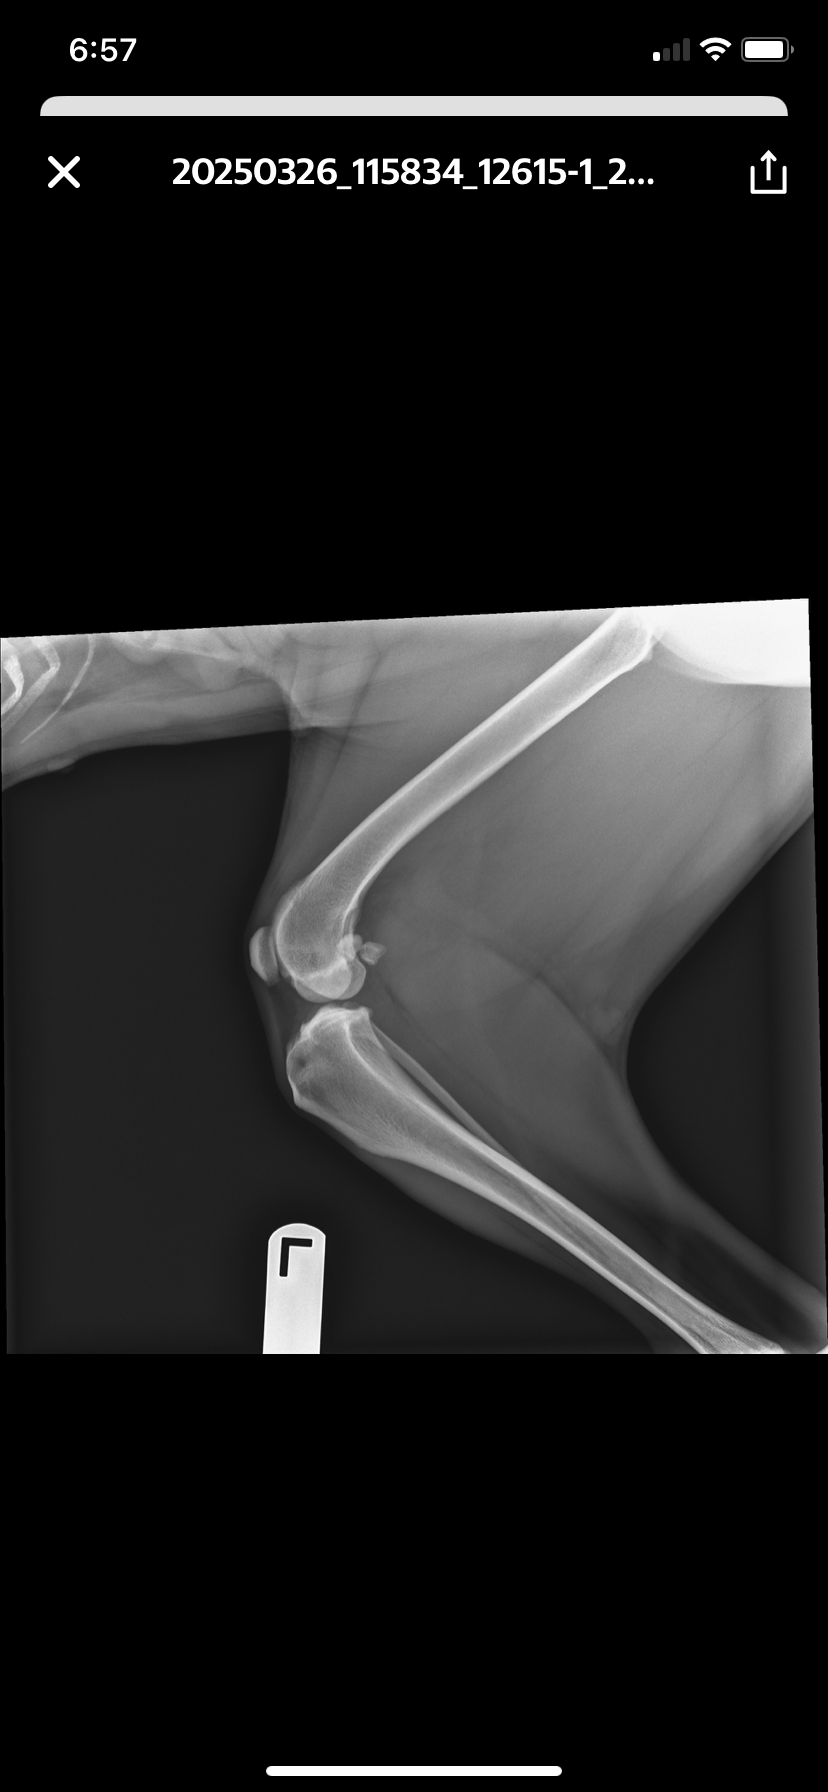

On 3/17/25 we went for a long walk, and per usual, we let her free to get her zoomies and explore the park. Unfortunately during her take off she tore a ligament, the CCL, which can be compared to a humans ACL. Knee injury. She also got a puncture wound on the pad of her paw, same injury side. After weeks of knee pain, and paw surgery and healing she was able to bear weight back on the left foot.

But, we are still left with the main injury - her CCL ligament. The past few weeks I’ve seen her pain increase, and mobility decrease at times. I’ve exhausted everything I can do for her myself, so we consulted with Skylos today, 6/3/25. I went for a consult to see if there was ANYTHING else I could do non-surgical.

Well, the answer is no. Due to the fact that she is not a little 20lb ankle biter - she’s a 60lb athletic, heavier dog. More weight needs to bear.